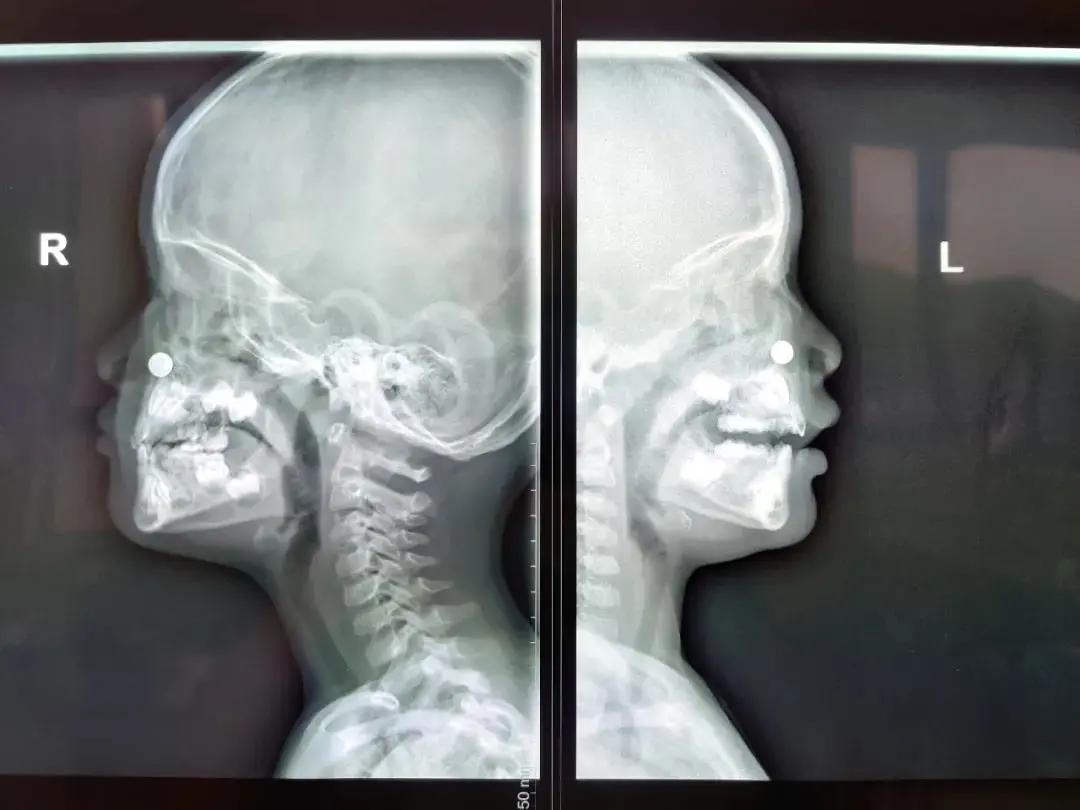

患儿是一位两岁的男孩,他妈妈告诉接诊的眼耳鼻喉科主任、主任医师陈瑜,这几天孩子的鼻子不通气、流鼻涕、咳嗽,前一天还出现发热症状。家长以为孩子感冒了,便带着孩子到当地医院的发热门诊就诊,该医院给孩子拍了X光片,提示“鼻腔异物”。

患儿X光片